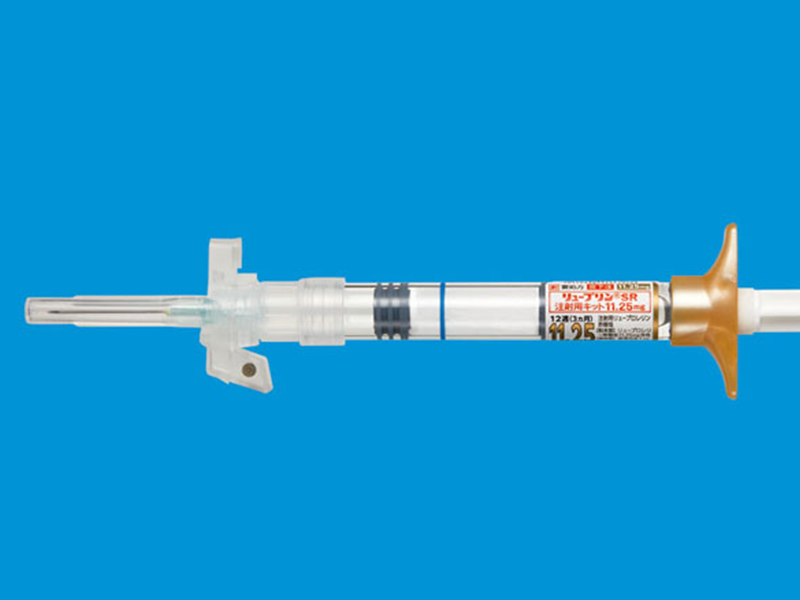

リュープリン

思春期の早い進行を抑える薬です。骨の成熟をゆっくりにすることで、身長が伸びる期間を延ばす効果があります。

身長治療で併用する薬剤

身長治療の効果を最大限に引き出すために、必要に応じて以下の薬剤を使用します。お子さまの成長状態や思春期の進行に合わせて、最適な組み合わせを選択します。

| 治療薬の種類 | 料金の目安 | 備考・使用目的 |

|---|---|---|

| 思春期 コントロール薬 (点鼻タイプ) |

月額40,000円 | 骨成熟の進行を緩やかにし、成長期間をサポートする点鼻薬です。 |

| 思春期 コントロール薬 (注射タイプ) |

月額60,000円 | 骨成熟の進行を緩やかにし、成長期間をサポートする注射薬です。 (月1回来院投与) |